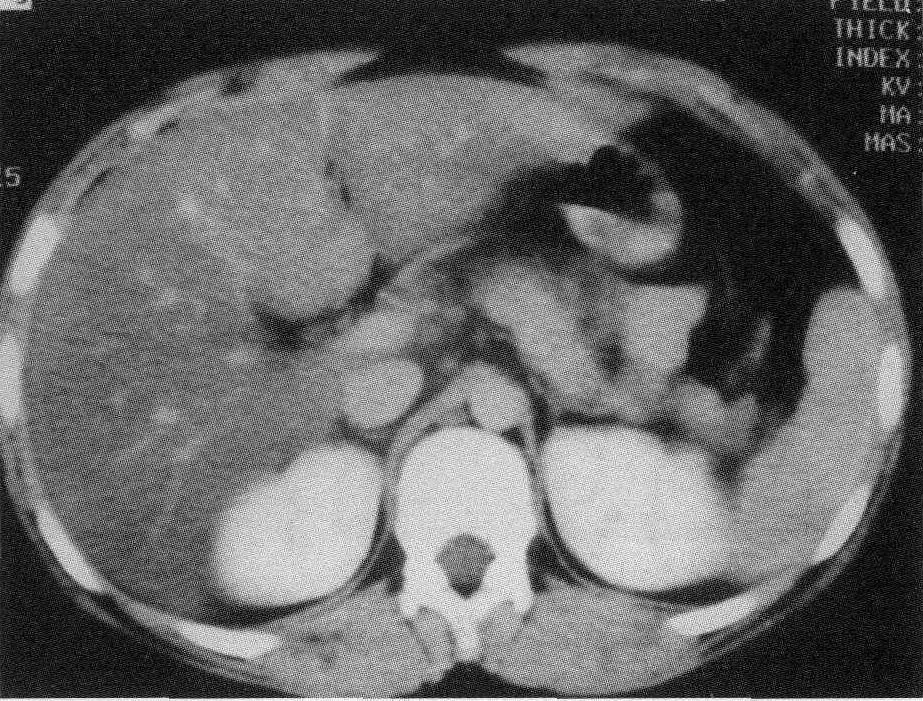

因为胰腺这玩意儿,位置非常隐蔽,藏在胃后面,被十二指肠、脾脏和肝脏等器官包围住了。

不过后来他在整理导师的病例资料时发现,在确诊十个月前,导师就曾做过一次平扫 CT 。

虽然当时没发现什么苗头,但带着结论回过头来分析,就能隐约看到到胰腺那里有病变的迹象。

在这样一个契机下,曹凯就想,既然人眼很难识别到平扫 CT 图像里,早期胰腺癌病变的迹象,那不如借助 AI 帮医生先筛查一遍。

并且因为平扫 CT 图的对比度太低,手动标注不太现实,所以他们都是在患者的增强 CT 图上标注。

标注的过程也是相当专业,医生们要勾画每一层 CT 图上肿瘤的二维图像,每张有十多二十层,非专业人士是一点都干不了。

画出来的十多张二维图像,叠加起来差不多就是整个肿瘤的三维图。